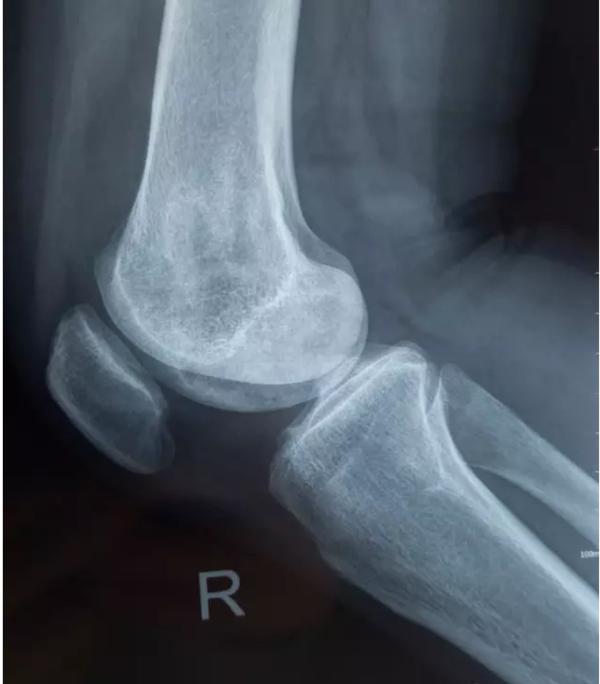

膝关节不均匀沉降术后患者X线片(下图)

中期:骨关节炎表现为膝关节持续性疼痛,活动后或上下楼梯时加重,压痛明显; X线片上可见增生的骨赘,关节间隙出现狭窄,多为不对称性狭窄。

晚期:骨关节炎表现为膝关节明显疼痛,休息后常无缓解,伴有活动受限,可并发畸形,X 线片可见关节周围有明显的骨赘形成,或可见游离体,关节间隙明显狭窄,甚至消失。